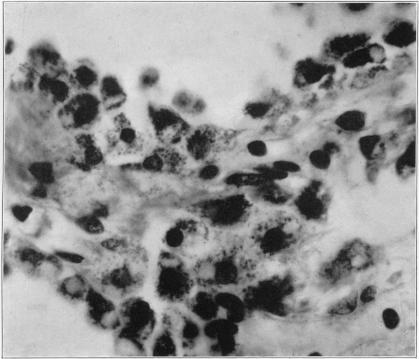

A Physio-Pathologic Study of the Choroid Plexus with the Report of a Case of Villous Hypertrophy.

J Med Res. 1924 Sep;44(5):521-534.11.